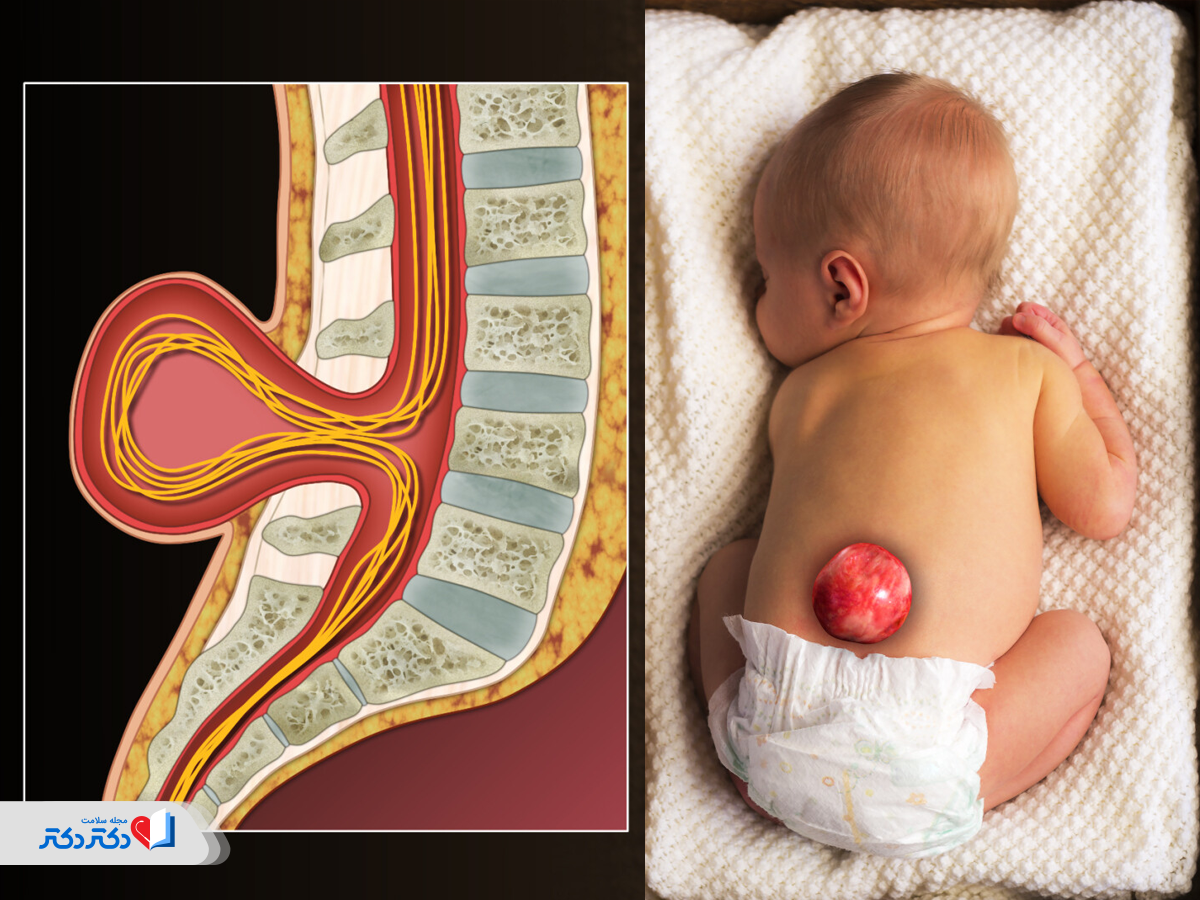

- مشکلات مغز و ستون فقرات: نقصهای لوله عصبی مانند اسپینا بیفیدا و آنانسفالی؛

- ناهنجاریهای ستون فقرات (مثل اسپینا بیفیدا باز)؛